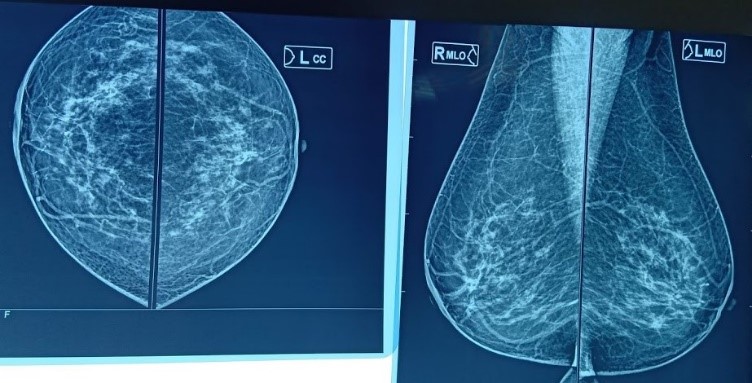

![]() |

Hình ảnh siêu âm và nhũ ảnh của bệnh nhân Vũ Thị M, 60t